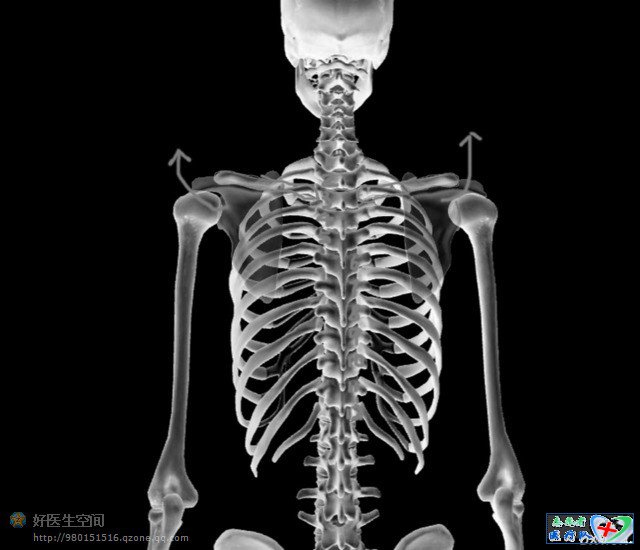

记住,正确的pose应该这样摆,当然你会说拍片位置角度本身就千差万别,这个就跟学心电图一样,你不能说人的体型千差万别你的心电图胸导就可以随便放吧,现在开始数骨头,数一数胸椎,数一数肋骨,拍的好的胸片胸锁关节平面正对第三胸椎,左右锁骨是对称的,看片是一眼看去先看这个这是个很重要的小技巧

这个看熟悉了,我用软件处理一下,现在在这个效果再次数骨头,熟悉了你就可以找几张胸片练一练眼力啦